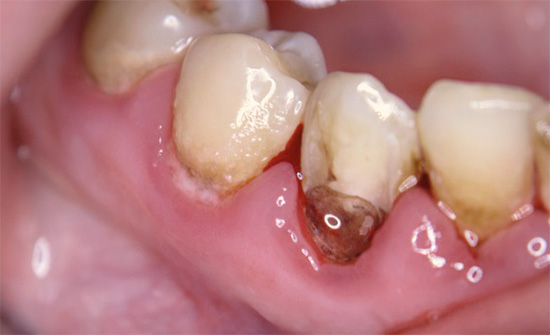

Se la malattia si sviluppa nella regione cervicale del dente, cioè in aree vicine alla gengiva, allora in questo caso stiamo parlando di carie cervicale. Una tale patologia ha anche un aspetto caratteristico: alla base, il dente sembra essere minato, a volte lungo l'intero perimetro, mentre la parte superiore della corona rimane spesso generalmente intatta.

Le fotografie seguenti mostrano alcuni esempi di carie cervicale: